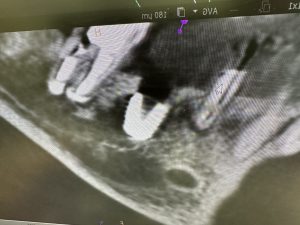

右下インプラントオペ

ISQ共に85.ITV90

バッチリ👌30分で終わり

狭窄歯列には減張しボナークにエムドゲイン

6w後には仮歯、印象